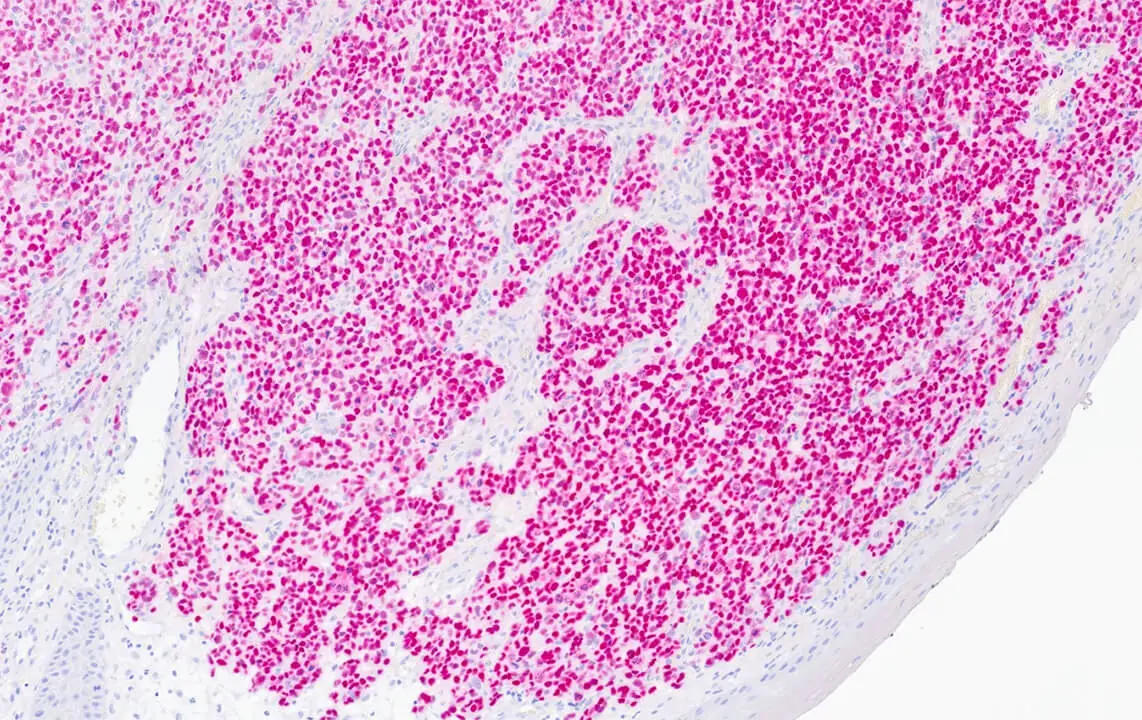

Melanoma: DAB staining of SOX10. Clone SOX10/991.

SOX10 is a nuclear transcription factor in the SOX (SRY Box) family of proteins, that plays an important role in neural crest development among other functions. As such it is expressed in cells of neural crest origin, including melanocytes and Schwann cells. It has been shown to be a sensitive and specific marker to aid in the diagnosis of melanoma, including spindle and desmoplastic subtypes, as well as a specific marker to aid in the differentiation of Malignant Peripheral Nerve Sheath Tumor (MPNST) from synovial sarcoma.

SOX10 is recommended for the detection of specific antigens of interest in normal and neoplastic tissues, as an adjunct to conventional histopathology using non-immunologic histochemical stains.